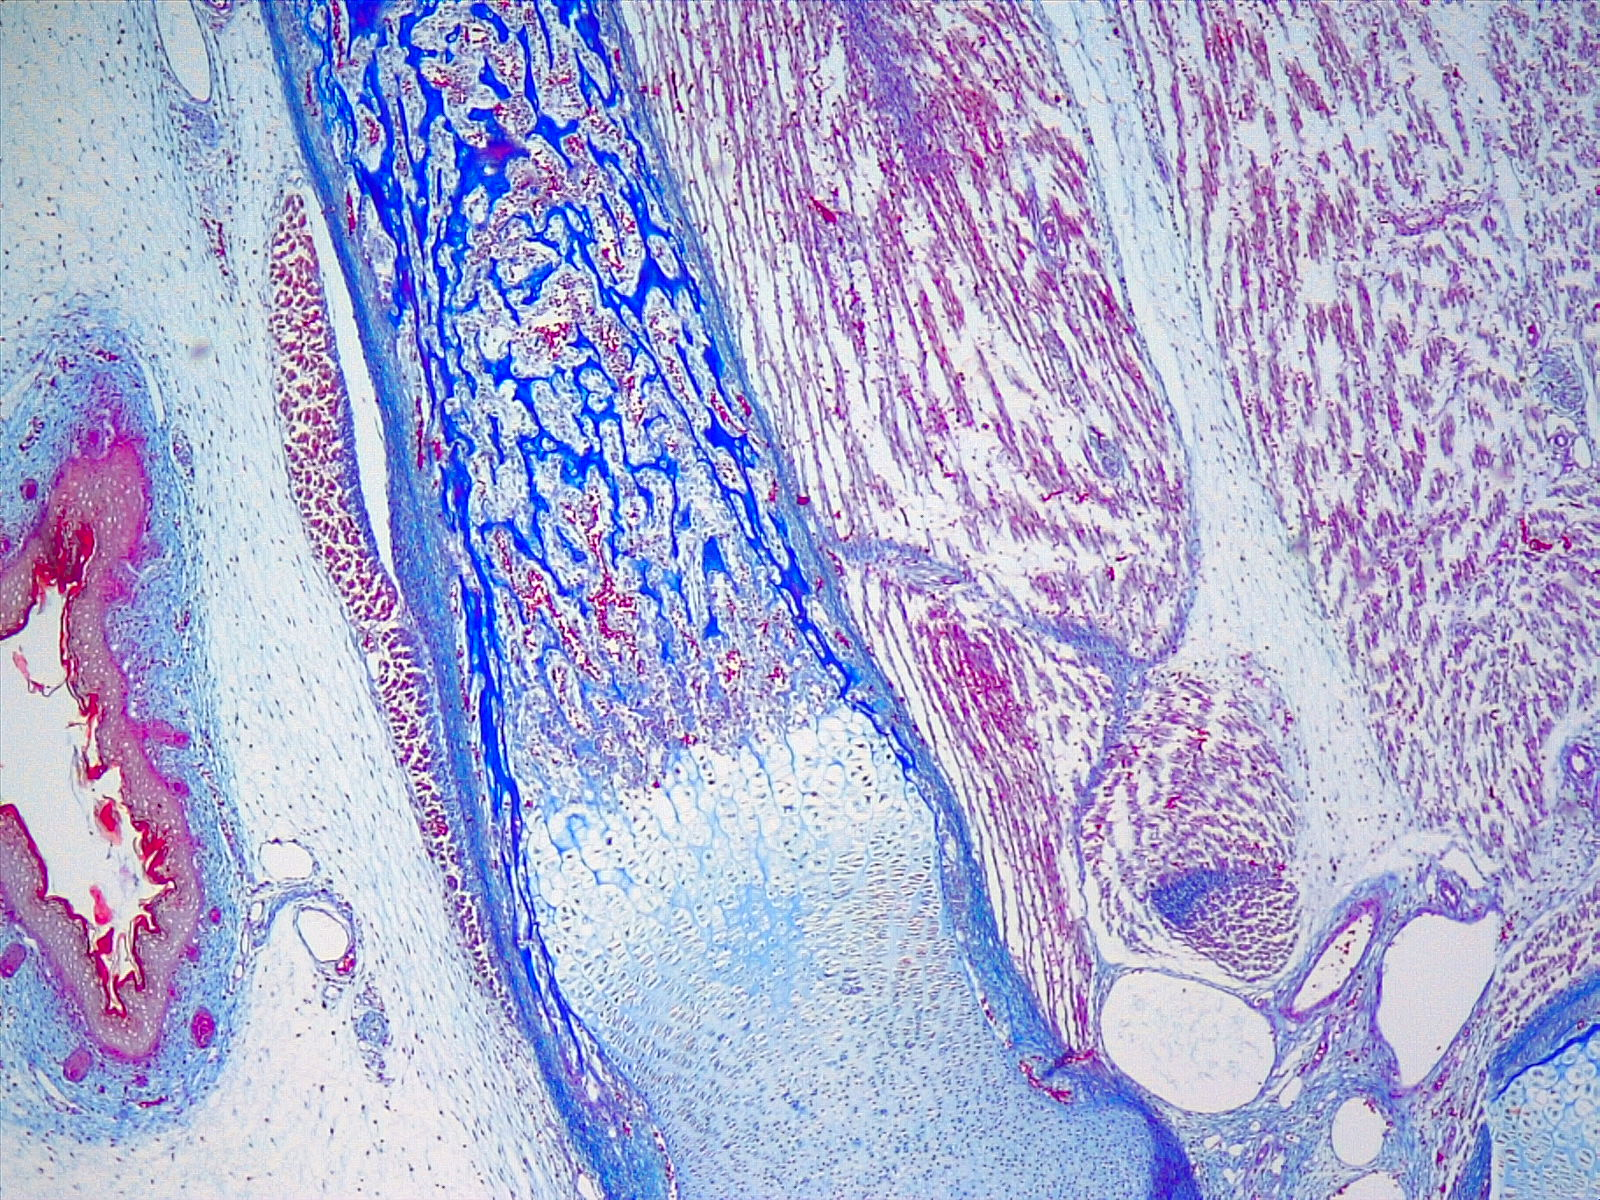

Frente a este punto, la profesora Francisca Villaroel menciona que “El Propedéutico es una instancia súper enriquecedora para los estudiantes, porque les permite acercarse a la vida universitaria a través de los diversos módulos, pero además es una instancia en la que pueden acceder a implementos que quizás en muchos colegios no hay por la falta de laboratorios, por ejemplo microscopios”.

Francisca Villarroel expresó que “he visto mucha motivación de los estudiantes por aprender ciencias, conocer cómo se forma nuestro cuerpo, además de mucho agradecimiento de ellos por la actividad, ya que para muchos era la primera vez que utilizaban un microscopio y podían observar muestras histológicas en el caso de mi módulo”.